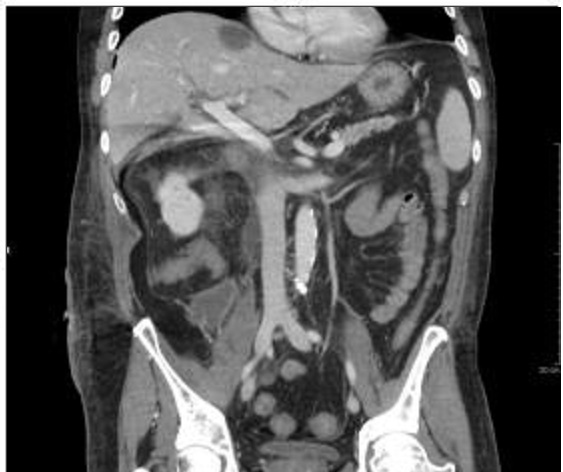

Image TDM de l'abdomen en

coupe coronale ( frontale)avec contrast iode . Veine

porte branche droit et gauche sont en vue |

Aspect normale de la veine

porte commun en coupe TDM coronale . |